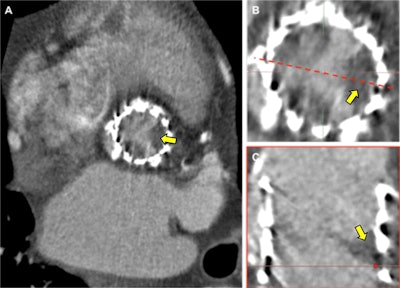

"We think heart attacks may actually more likely be related to disease activity inside the arterial wall," said Dr. Alastair Moss, a research fellow in cardiovascular imaging at the University of Edinburgh, whose special interests include combining advanced imaging modalities to better understand the pathophysiology of cardiovascular disease. "This is where our current research studies are focusing. We're using novel molecular imaging techniques such as PET/CT so that we can now measure disease activity inside coronary plaques."

Through the facility's PET/CT program, supported by the British Heart Foundation and Wellcome Trust, the researchers are seeking to find out whether this modality can be used to predict future heart attacks and help doctors decide who needs more aggressive treatment.

The hypothesis under investigation is: Does identifying patients with increased disease activity in the coronary arteries help identify patients at increased risk of having a heart attack? It will be one of the first multicenter PET/CT studies to investigate whether the radiotracer F-18 fluoride can be used prospectively to identify patients at risk of recurrent heart attacks, according to Dweck. He expects the results to be available in 2021.